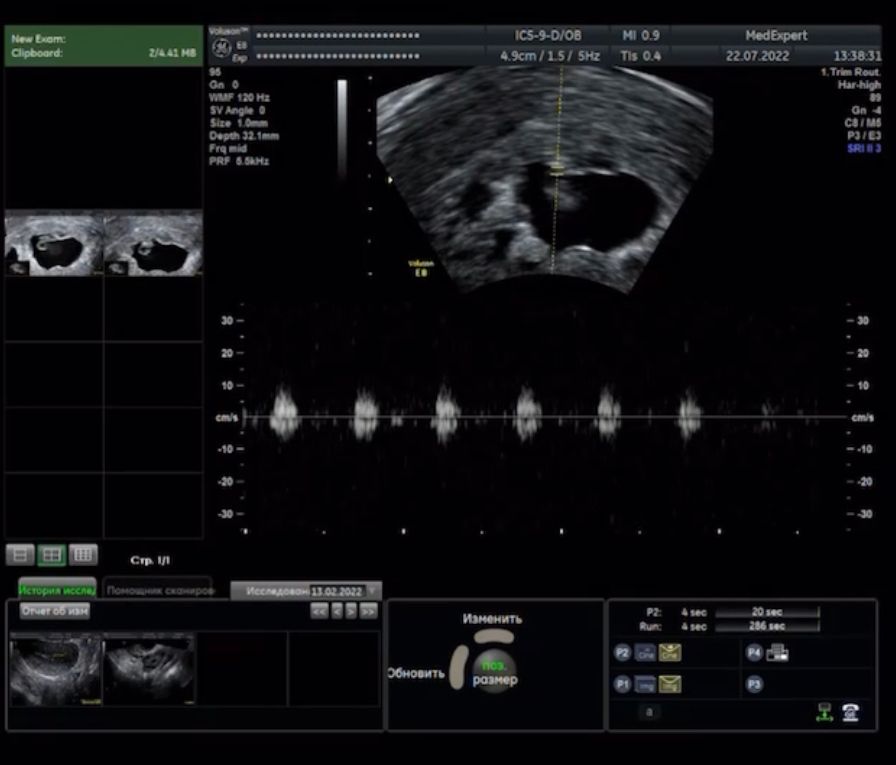

А, это значит сегодня у нас первое узи, ждала я его с особым трепетом и переживаниями)

Сердцебиение отличное, единственное нашли небольшую отслойку, в общем из-за неё выла серия постов с выделениями 😂